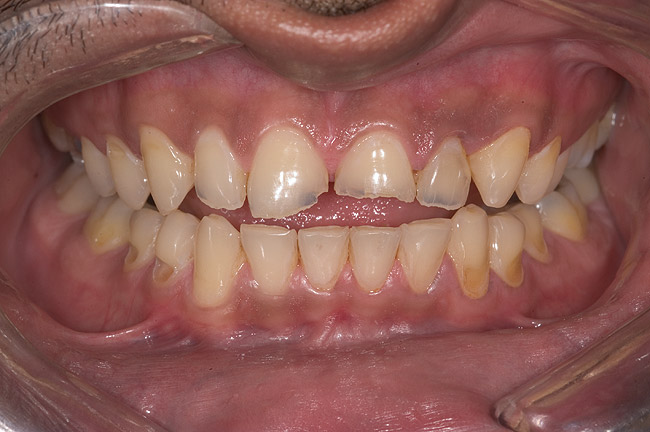

A 20-year-old male patient presented with irregular upper anterior teeth and was unhappy with his smile (Figure 4). He complained of occasional generalized mild sensitivity. Dental treatment history revealed that he had occasional dental work done in the past. Two weeks previously, he had severe pain in tooth No. 10, which was treated endodontically, and he was then referred to the author’s practice for management of anterior wear. Tooth No. 3 had a broken amalgam restoration.

Examination revealed that palatal surfaces of teeth Nos. 6 through 11 showed severe loss of tooth structure, with mild wear on the lower incisors and loss of anterior guidance (Figure 5 through Figure 7). The palatal TSL was consistent with the clinical picture presented by patients with gastric reflux. A detailed medical history was taken, and the patient complained of having heartburn and acidity at least 4 out of 7 days a week. He had never sought treatment for it and used over-the-counter medication when needed. He was a nonsmoker, with occasional intake of alcohol. He had a high-stress job with irregular meal times. A thorough smile and dental analysis11 was carried out; the findings appear in Table 2.

Figure 4  Preoperative smile view.

Figure 4

Figure 5  Thinning of the labial enamel and noncarious cervical lesions.

Figure 5

Figure 6  1:1 view demonstrating severe loss of tooth structure due to palatal erosion.

Figure 6

Figure 7  Palatal surface showing loss of form due to enamel dissolution.

Figure 7